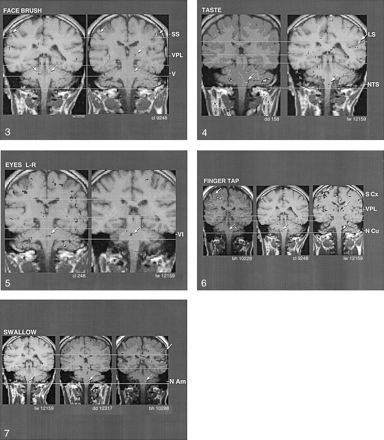

Coronal images obtained with motor tasks and sensory stimuli used to activate different brain regions (arrows) in the same individual. These tasks and stimuli correspond to the trigeminal (V), solitary (NTS), ambiguus (N Am), and cuneate (N Cu) nuclei.

A semi-diagrammatic representation of the location of brainstem nuclei relevant to the present study is presented in Figure 9. Figure 1 shows a composite comparison of the regions of BOLD activity in the lower brainstem that were observed in a single subject in the same brain section, in relation to the performance of the four sensory and motor tasks. Note the distinctly different regions of activation with each of the tasks.

Figure 2 shows a comparison of the regions of BOLD activity in the same individual in the same brain section obtained with two tasks that involve closely adjacent, but different, CN motor nuclei. The task of alternating between smiling and puckering the lips was correlated with BOLD activation in the region of the facial nucleus (CN VII). By contrast, eye movement (ie, shifting the eyes laterally with alternating left-to-right movement) was correlated with BOLD activation in the pons in the region of the abducens nucleus (CN VI), which provides the motor innervation of the lateral rectus muscles of the eye. The abducens nucleus is near the midline, whereas the facial nucleus is lateral to it, at about the same level of the neuraxis. Note that the region of BOLD activation in the cortex corresponded to the homuncular region of the face, consistent with the activation in the brainstem. Also shown in Figure 2 is the cross-correlation time series data. The upper part of each of the traces shows the time course of the BOLD signal change in these ROIs. The lower part shows the time course of the stimulus input; the peak represents the activity of the paradigm, which alternates with the baseline.

Coronal images show that facial and eye movements activate different adjacent brain regions that correspond to the facial and abducens CN nuclei, respectively. Cross-correlation analysis was performed between the onset and termination of the movements and the BOLD signal change in these pontine regions of activation. C1 indicates the C1 level of the spinal cord; M Ctx, motor cortex; VI, CN VI, and VII, CN VII.

Coronal images show the similarity of activation (arrows) produced by brushing the face, which corresponds to the region of the trigeminal main sensory nucleus (V), in two individuals. Note activation of nucleus ventralis posteromedialis (VPL) in one of the individuals and of somatosensory cortex (SS) in both individuals.

Figure 4 shows interindividual consistency in BOLD activation in the region of the superior level of the NTS in the medulla oblongata, in correlation with the taste stimulus. Note the activation of the sensory cortex (right image) at the level of the lateral sulcus, which closely corresponded to the homuncular tongue region.

Figure 5 shows interindividual reliability in the region of BOLD activation in correlation with left-to-right eye movement. The pontine location of activation near the midline was consistent with activation of the abducens nucleus (CN VI). Figure 6 shows that the region of BOLD activation in relation to finger tapping was consistent among three individuals. This finding corresponded to the region of the nucleus cuneatus, which receives afferent activity from the hands. In addition, the region of BOLD activation in the sensory cortex corresponded to the homuncular region for the fingers (note that this region of activation was superior to that in the face in Figure 2). Furthermore, in one subject (right image), BOLD activation was evident in the somatosensory thalamus (region of the nucleus VPL); this finding was consistent with afferent activation from the fingers.

Figure 7 shows the BOLD activation pattern that was correlated with dry swallowing (ie, Mendelsohn maneuver). This movement required activation of the nucleus ambiguus of the medulla oblongata. The images show that the region of the nucleus ambiguus was consistently activated in three individuals during the performance of this task. Note the activation at the inferolateral aspect of the motor cortex just superior to the lateral sulcus (upper arrow, right image), which corresponded to the homuncular pharyngeal region.

Coronal images show the similarity of activation (arrows) in the region of the NTS, produced by tasting a sweet-sour-salty-bitter mixture, in two individuals. LS indicates the lateral sulcus.

Coronal images shows the similarity of activation (arrows) in the region of the abducens nucleus (VI), produced by voluntary left-right eye movement, in two individuals.

Coronal images shows the similarity of activation (arrows) in the region of the nucleus cuneatus (N Cu), produced by tapping the fingers against the thumbs, in three different individuals. Note the activation of the VPL and somatosensory cortex (S Cx) in the finger homuncular region as well.

Coronal images shows the similarity of activation (arrows) in the region of the nucleus ambiguus (N Am) in three individuals. These findings were correlated with dry swallowing (ie, Mendelsohn maneuver).